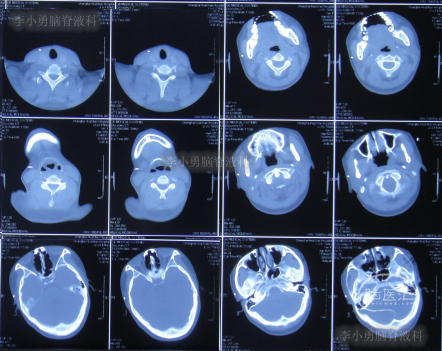

家属为进一步明确病因即2016年4月4日,第2次就诊并住入第二家的上海市静安区的某三甲医院,复查头颅影像后(图-3、图-4),给予按癫痫进行治疗。

图-3:2016年4月4日头颅CT

图-4:2016年4月4日头颅影像